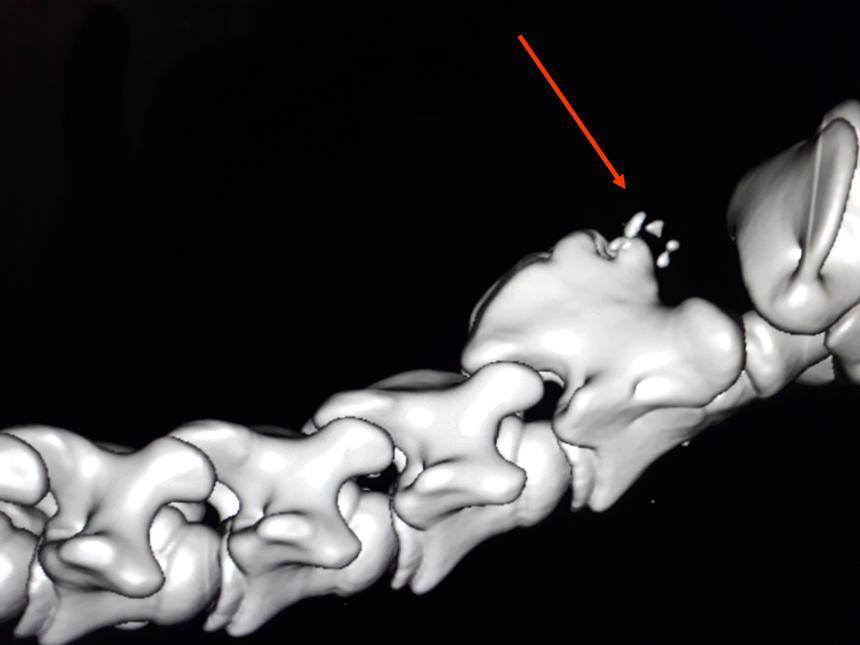

А помните, я упоминала про мою очередную поездку в ветшколу/клинику CIRALE ? Вот их новый ИРМ

Причем все не особо дорого, потому что работают студенты и ветеринары-стажеры по базовым манипуляциям, и часть расходов клиники покрывается программами Евросоюза и французским фондом EPERON (распределяющим в год 10 млн евро на инновации в конной отрасли, откуда деньги ? - с тотализатора). Лошадей туда везут со всей Европы, аж со Скандинавии. Особая слава у CIRALE - это диагностика проблем локомоторного аппарата, другими словами - проблемы всего, что влияет на движения (суставы, сухожильно-связочный, позвоночник, повреждения мягких тканей и тп).